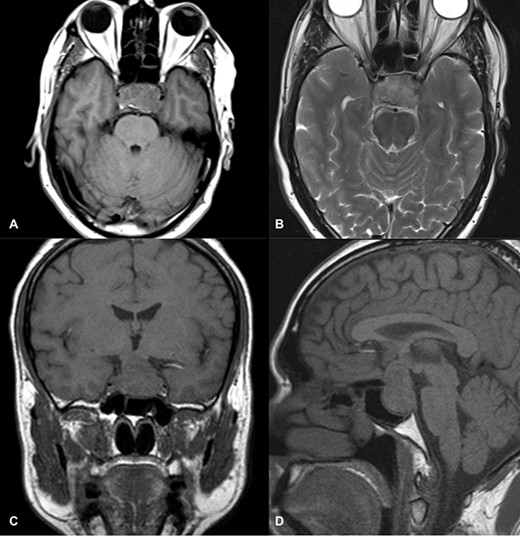

MRI imaging showed a 2 × 1.6 × 1.6 cm sized sellar lesion arising from the pituitary fossa with an intrinsic high T1 signal in the periphery, extending superiorly in the suprasellar region and laterally, causing a mass effect on the left cavernous sinus. A signal void was seen in T2-weighted images suggestive of hemorrhage (Fig. 3).

MRI images of post-contrast sagittal T1 (A), sagittal T1 (B), axial T2 (C), and post-contrast axial T1-weighted images (D) showing a 2 cm × 1.6 cm × 1.6 cm sized sellar lesion arising from the pituitary fossa extending superiorly in the suprasellar region and laterally causing a mass effect on the left cavernous sinus with intrinsic high T1 signal in the periphery and signal void on T2-weighted images suggestive of hemorrhage.